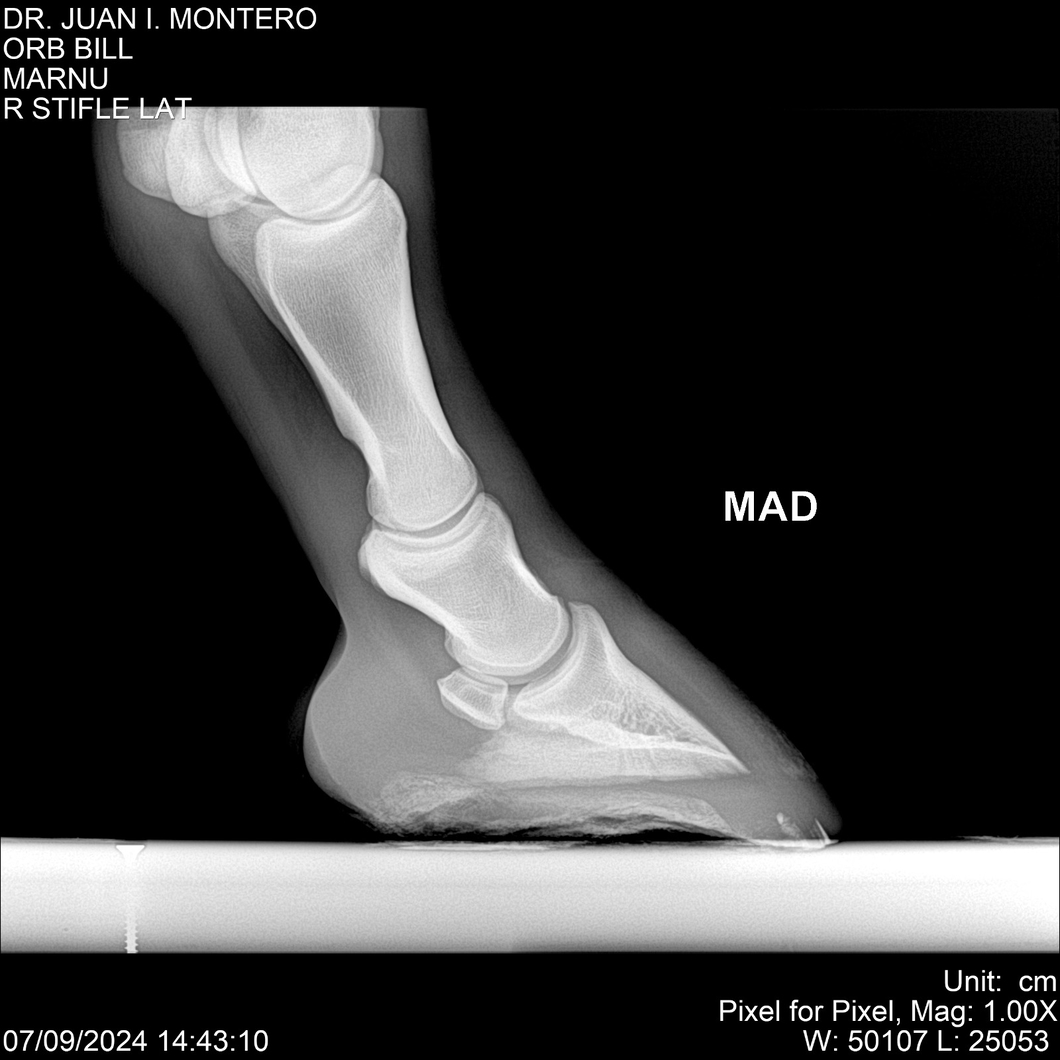

LOTE 7, ORB BILL 🔥 🔥 🔥 Lote Anterior Volver al remate Lote Siguiente Ficha Contacto Montevideo - Ficha del Lote Identificador: #282523 Categoría: Yeguarizos Montevideo - 83 Visualizaciones ClicData Contacto Empresa: Abelenda N. R., Walter Hugo Nombre*: Teléfono* : E-mail* : Mensaje Enviar Registrese gratis Este contenido Exclusivo está disponible sólo para usuarios registrados Ingresar